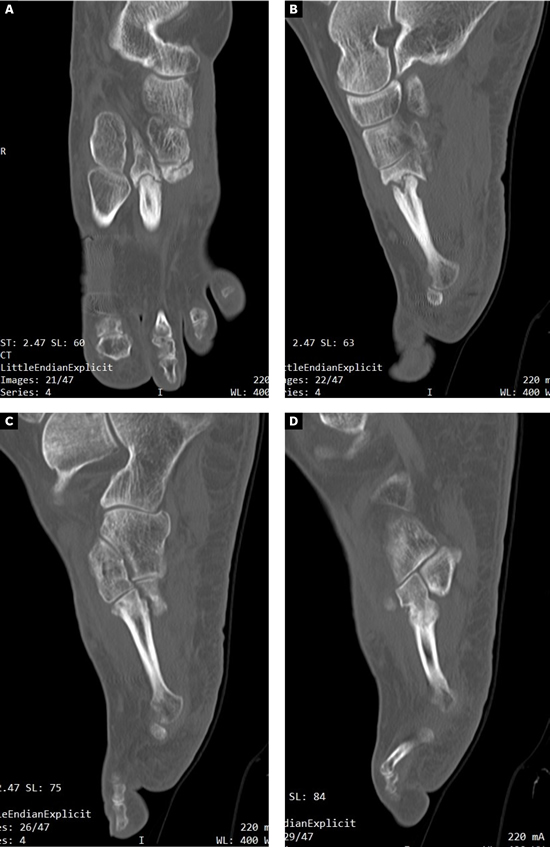

El postoperatorio transcurrió sin incidencias y se realizaron curas postoperatorias con suero fisiológico y povidona yodada a los 7, 21 y 49 días postoperatorios. A las 6 semanas y 2 días (30 de julio de 2015) se realizó TAC de control que fue valorado el 7 de agosto de 2015 (7 semanas y 3 días tras la intervencion). Este TAC evidenciaba buena integración del injerto. Tras este hecho, junto con la favorable evolución clínica, se permitió a la paciente la carga parcial con bota tipo Walker durante 3 semanas para posteriormente comenzar a utilizar calzado convencional de forma progresiva.

A los 5 meses de la intervención se solicitó nuevamente un TAC comparativo que se realizó el 20 de noviembre de 2015 (Figura 6) que evidenció la integración completa del injerto y la consolidación del 4.º metatarsiano. La evolución clínica de la paciente fue muy positiva con ausencia completa de dolor realizando todas las actividades de la vida diaria con normalidad. Con fecha 25 de mayo de 2016 (11 meses postoperatorios) se realizó última visita de la paciente encontrándose esta en perfectas condiciones y dando el alta a la paciente. La paciente ha sido seguido posteriormente con revisiones anuales durante 4 años (hasta 2019) sin ninguna alteración.

Imagen 6. TAC postoperatorio a los 5 meses. 6A. Imagen del 2º metatarsiano que muestra integración del injerto con la placa dorsal. 6B. Imagen del 4º metatarsiano que muestra consolidación del 4º metatarsiano.